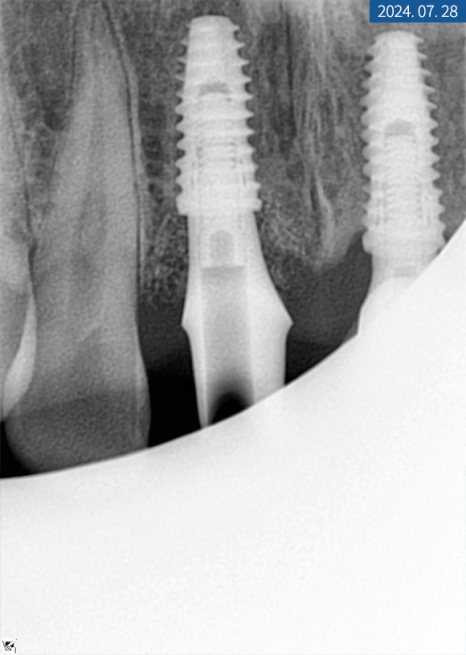

20대 남성분의 X-ray 사진

X-ray 상 앞니 손상과 치근 염증이

심하다는 결과를 봐서는 발치가 필요해 보였으며

좌측 하악 어금니도 뿌리 밑에 염증이 생겨

치아 보존이 힘든 상황이었습니다.

그만큼 치아 강직과 만성 복합치주염으로 인한

난발치 상황이었죠.

우측도 파열돼있었지만

우선 치주 치료를 하면서 지켜봐도

좋을 것 같다는 판단이 들었습니다.